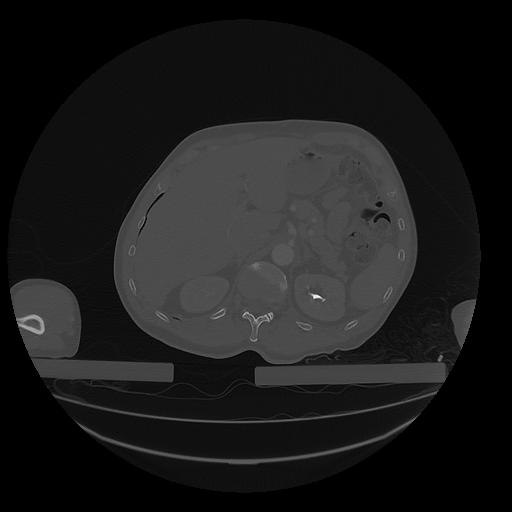

31 PULMON,CE,Vol,1.0,PULMON,,